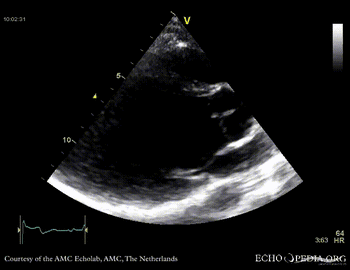

Case 10